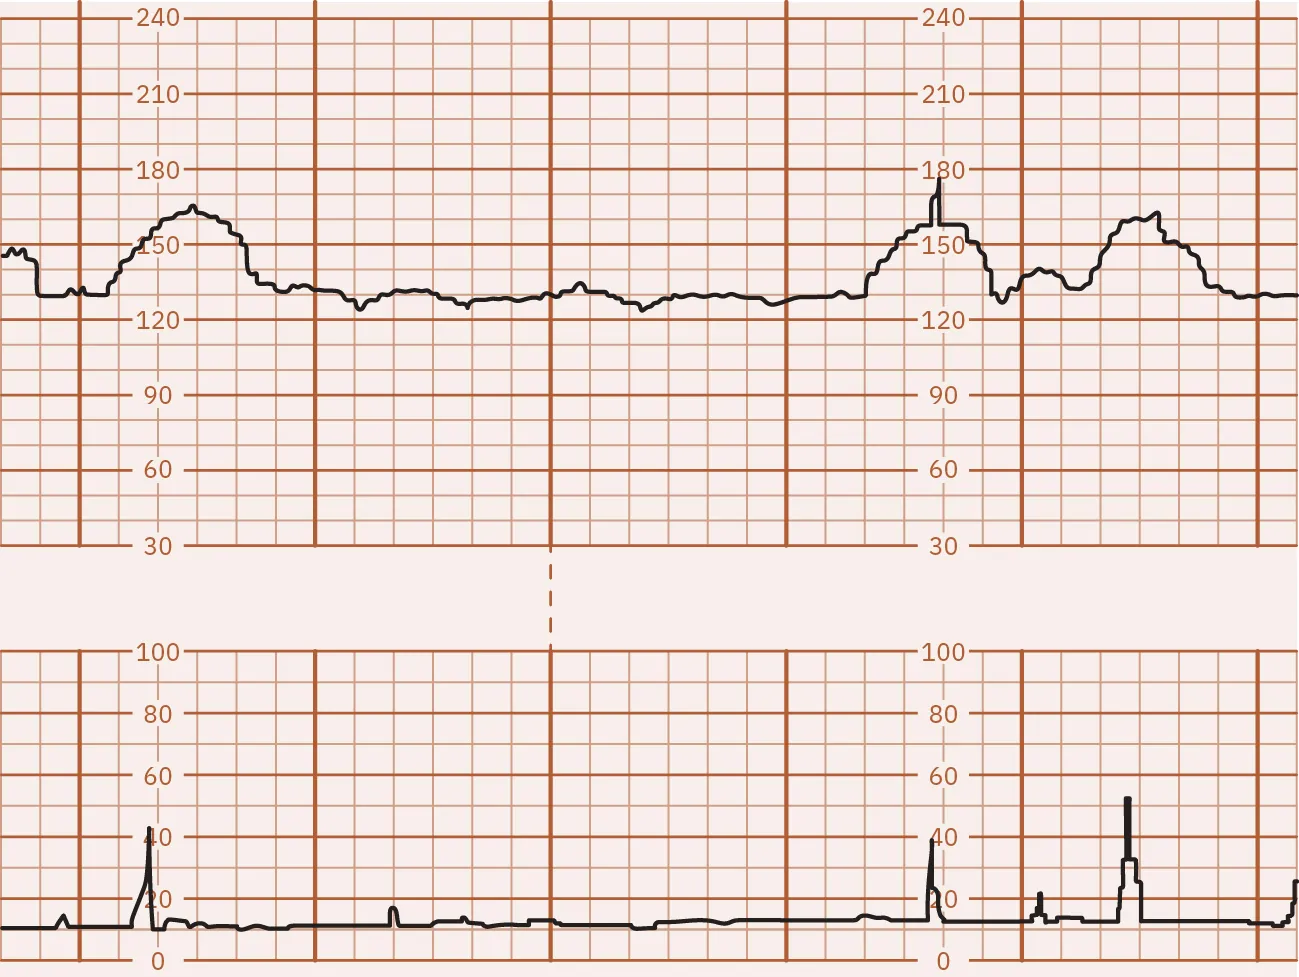

A nonstress test (NST) is a noninvasive test for fetal well-being that provides a graphic of the fetal heart pattern in relation to the movement of the fetus (Figure 13.10). The external fetal and uterine contraction monitor is used to perform an NST. This test places no stress on the fetus. A nonstress test can be performed starting at 28 weeksโ€™ gestation (U.S. National Library of Medicine, 2021a).

Fetal monitor tracing graphic depicting a reactive NST. Top strip indicates spikes at same times lower strip indicates spikes.

Figure 13.10 Reactive NST The FHR accelerations are linked with the fetal movements in the uterine contraction tracing. In this illustration, the FHR increased at least 15 beats per minute (bpm) above the baseline of 130 two or more times in this 10-minute tracing. (attribution: Copyright Rice University, OpenStax, under CC BY 4.0 license)

If the fetal heart rate increases by at least 15 bpm above the baseline for 15 seconds for a fetus at 32 weeks or greater, or 10 bpm for 10 seconds in the fetus less than 32 weeks, two or more times during a 20-minute testing period, it is considered a reactive NST and is a reassuring result. If there are insufficient accelerations of the fetal heart rate within the 20- to 40-minute window or the accelerations do not meet the required criteria, the NST is nonreactive. However, a nonreactive result does not necessarily indicate a health problem. The fetus may have been sleeping and not easily awakened. Certain medications taken during pregnancy may also cause a nonreactive result. The health-care provider will review the results and determine if additional testing is needed to find out if there is a cause for concern (U.S. National Library of Medicine, 2021a).